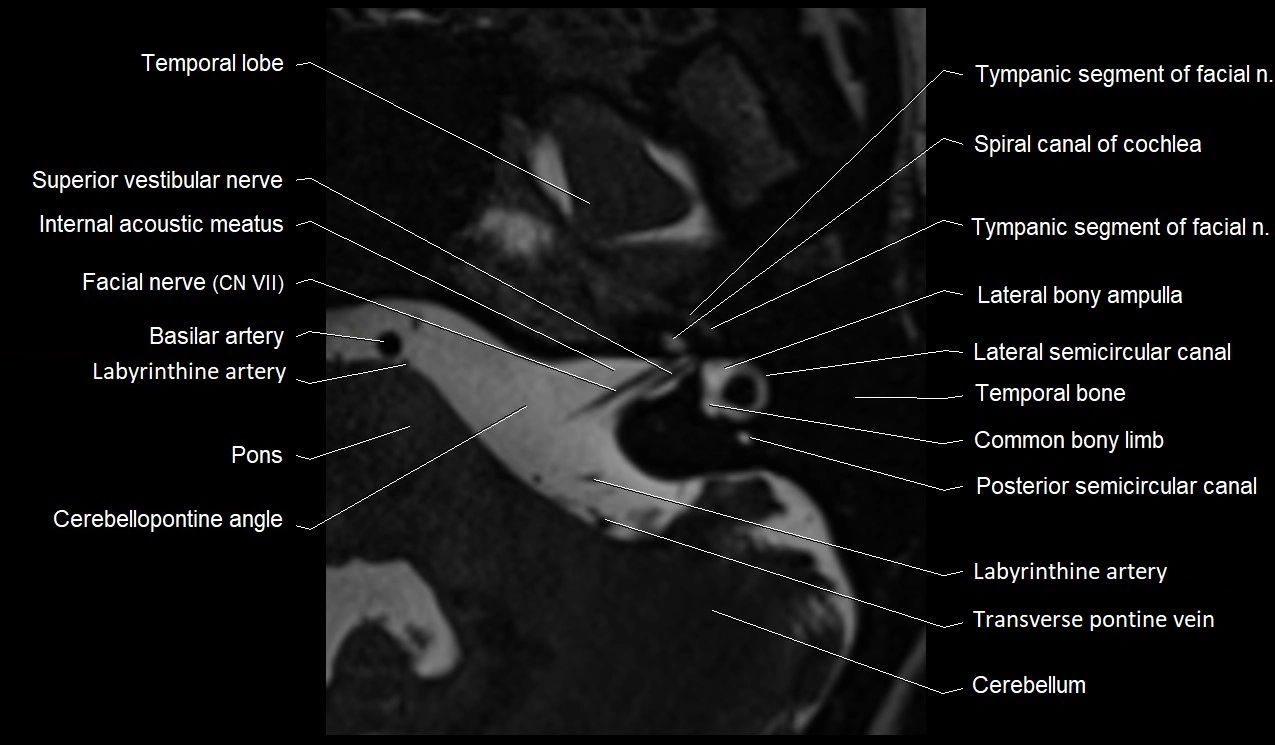

image